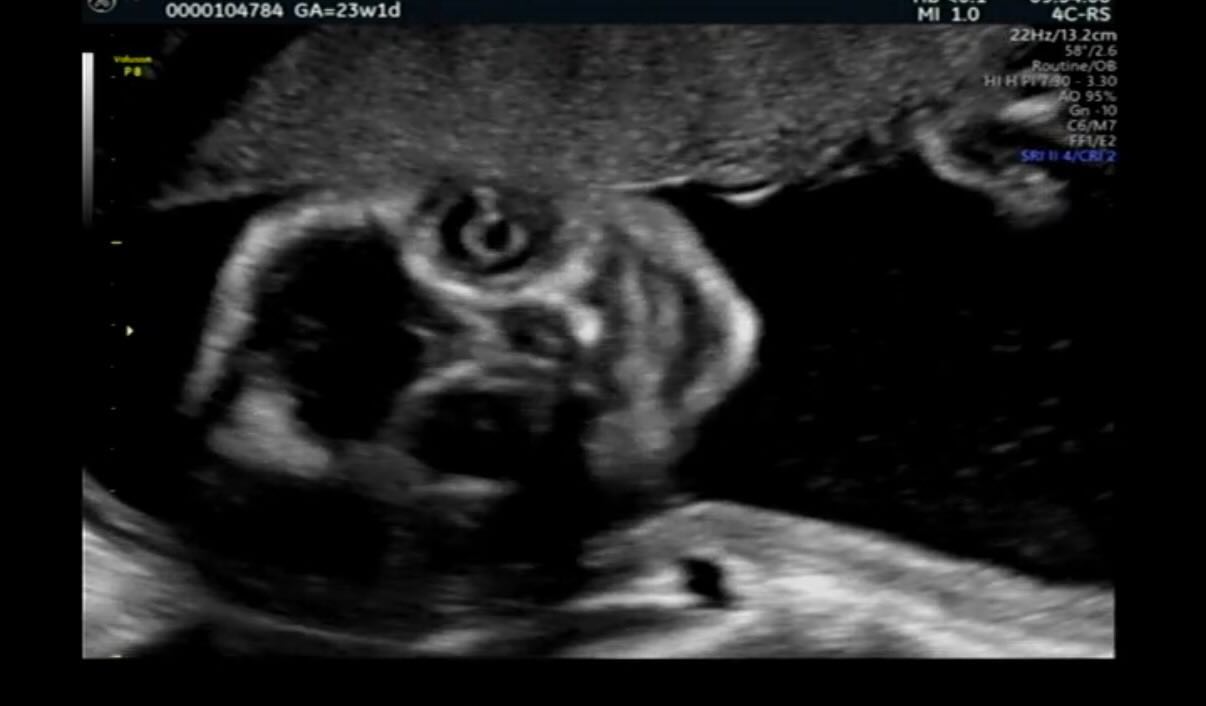

白黒でコントラストが強く、輪郭がぼやけがちなエコー写真。

カメラ目線のエコー写真

投稿されたのは、妊娠25週の頃に撮影されたエコー写真と、生後7日の可愛らしい赤ちゃんの写真2枚。エコーには、こちらをぎょろりと見つめ、ニヤリと笑っているようなちょっと怖い表情が写っていました。

初めての妊娠だったYukiさんは、この写真を見たとき「こんなものなのかな?」とも思いつつ、夫婦2人で「めっちゃこっち見てるね。ホラーだね」と笑い合っていたそうです。

その後、他の人が「これよりホラーなエコーありますか?」と妊娠中のエコー写真を投稿しているのを見かけ、自分のエコーもかなりホラーだったことを思い出してリプライ。すると「優勝です」「夢に出そう」といったコメントが多数寄せられたのだとか。